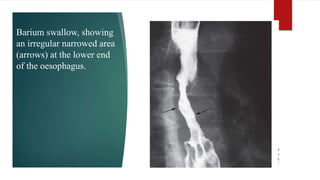

Barium swallow, showing

an irregular narrowed area

(arrows) at the lower end

of the oesophagus.

Barium swallow, showing anirregular narrowed area (arrows) at the lower end of the oesophagus.